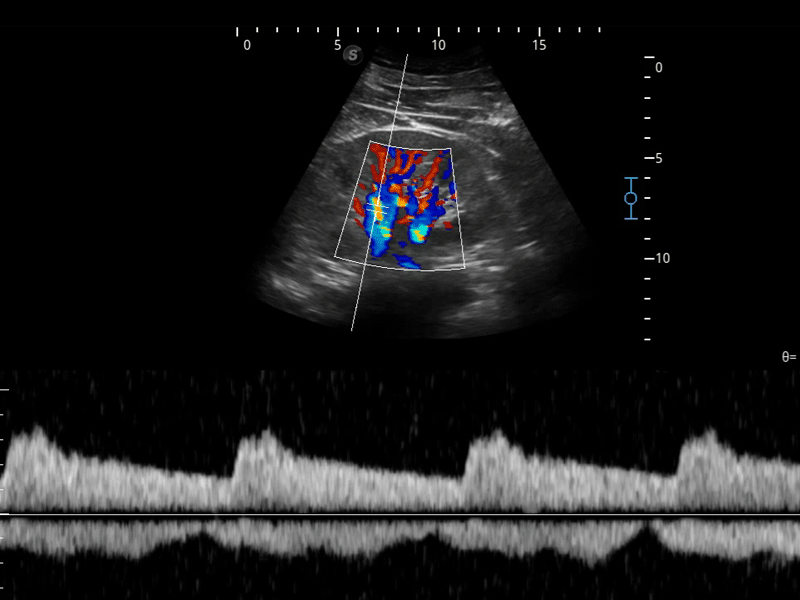

開(kāi)立醫(yī)療通過(guò)不斷的技術(shù)創(chuàng)新,為大眾的生命健康提供持續(xù)關(guān)愛(ài)。P12 Plus采用全新一代超聲成像平臺(tái),新平臺(tái)旨在將真實(shí)還原組織解剖結(jié)構(gòu)作為首要目標(biāo)。平臺(tái)采用全新集成化硬件模塊,搭載新一代芯片,系統(tǒng)性能得到大幅提升,為您的診斷提供了豐富的臨床信息。優(yōu)異的圖像表現(xiàn),豐富的探頭配置,全面的應(yīng)用功能,為您日常診斷提供了可靠的助手。

彩色多普勒超聲診斷系統(tǒng)